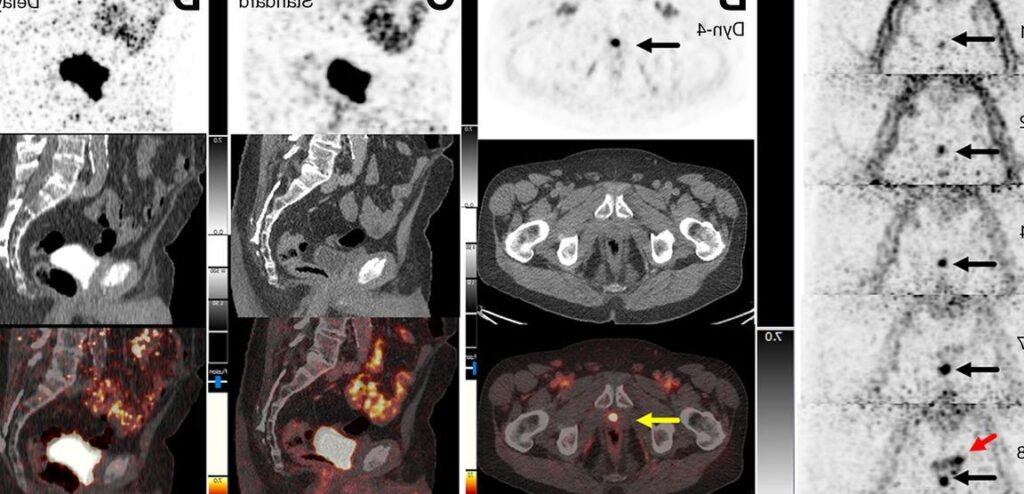

La Tomographie par Émission de Positrons (TEP) au moyen de la Choline est une technique d’imagerie médicale innovante qui joue un rôle prépondérant dans le diagnostic et l’évaluation de la cancer de la prostate. Cette méthode s’appuie sur l’utilisation d’un marqueur radioactif, la Choline marquée avec du fluor-18 ou du carbon-11, qui se concentre spécifiquement dans les cellules cancéreuses prostatiques. Ainsi, le TEP Choline permet d’identifier avec précision les tumeurs primaires et les métastases, même lorsqu’elles sont situées hors de la prostate. Il devient alors possible d’obtenir une carte détaillée de l’activité tumorale, ce qui est primordial pour établir des stratégies thérapeutiques adaptées et personnalisées pour chaque patient.

Dans le tableau comparatif ci-dessus, nous observons que chaque modalité de diagnostic possède ses propres avantages et limites en termes de sensibilité et de spécificité. La TEP Choline se distingue par sa capacité à détecter la récidive et à évaluer l’étendue des métastases lymphatiques, fournissant ainsi des informations cruciales qui ne sont pas toujours accessibles via les autres méthodes.

La TEP à la choline (tomographie par émission de positons) est une technique d’imagerie médicale qui utilise un traceur radioactif, en l’occurrence la choline marquée par un isotope radioactif. Cette technique est utilisée pour détecter les cellules cancéreuses actives dans le corps. Dans le contexte du cancer de la prostate, la TEP à la choline peut aider à identifier des métastases osseuses ou dans d’autres tissus qui ne sont pas toujours visibles avec les méthodes d’imagerie conventionnelles. Elle permet ainsi de mieux évaluer l’étendue du cancer et de guider le plan de traitement.

Les avantages de la TEP à la choline par rapport aux autres méthodes d’imagerie pour la détection des métastases du cancer de la prostate incluent une sensibilité et spécificité élevées, la capacité à détecter de petites lésions qui ne sont pas visibles avec le CT ou l’IRM, et la possibilité de réaliser une évaluation globale de l’étendue de la maladie dans tout le corps en un seul examen.